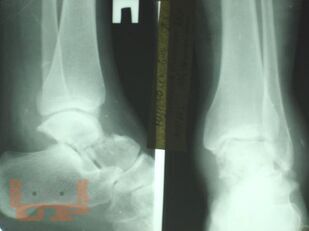

Чрескостный остеосинтез аппаратами внешней фиксации при лечении повреждений таранной кости

Учебно-методическое пособие содержит необходимую информацию для врачей по вопросам механизма повреждения, клиники, диагностики, осложнений и лечения переломов таранной кости. В пособии представлены биомеханические особенности дистального отдела нижней конечности. Основное внимание уделено проблеме лечения переломов таранной кости, а также осложнений переломов и переломо-вывихов таранной кости в виде развития аваскулярного некроза таранной кости. Приведены компоновки аппаратов внешней фиксации при различных типах повреждений.

В пособии обобщен более, чем 30-летний опыт лечения пациентов с переломами и переломо-вывихами таранной кости.